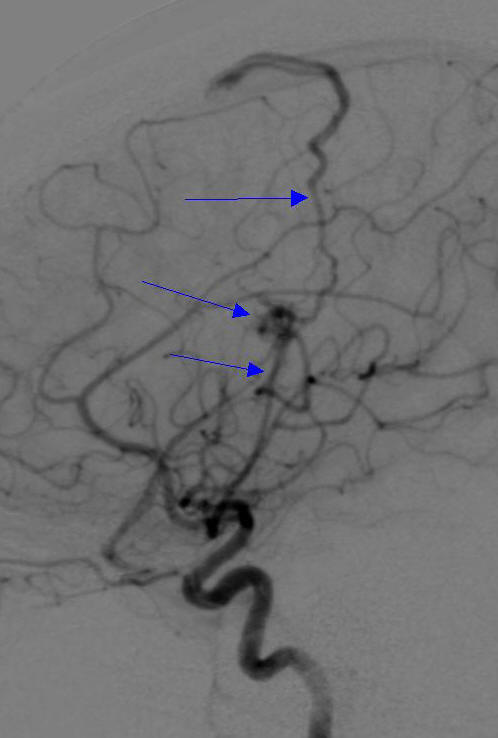

病例2